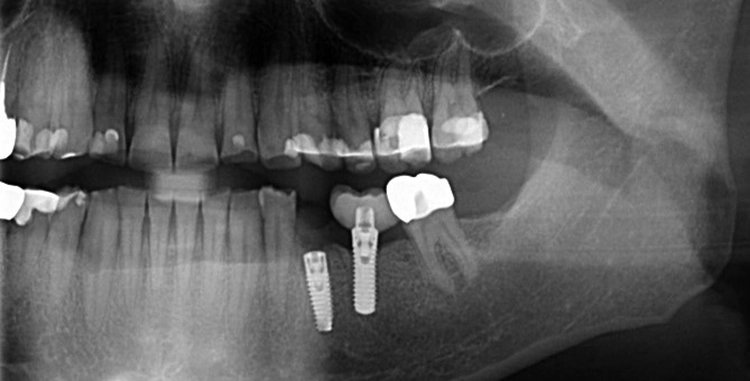

5. Multiple Sofortimplantationen in Zusammenhang mit internem Sinuslift

Beim vorliegenden 54-jährigen Patienten mussten aufgrund von lokaler Parodontitis die Zähne 25, 26 und 27 entfernt werden. Im apikalen Bereich lag jedoch gesunder Kieferknochen vor, sodass eine Sofortimplantation möglich war. Aufgrund der guten Einsichtbarkeit des Operationsgebietes nach Zahnextraktion konnte in diesem Fall flapless vorgegangen werden.

In regio 26 konnte das Implantat dabei komplett apikal im gesunden Knochen verankert werden. In regio 27 jedoch wurde lediglich eine Restknochenhöhe von 8 mm bestimmt. In diesem Fall wurde die Sofortimplantation mit einer internen Sinusbodenelevation nach Summerset kombiniert.

Da zur Aufweitung der Trifurkation die Densah Versah Burs im Rückwärtslauf eingesetzt wurden, kann durch die Osseodensifikation auch der Kieferhöhlenboden bis zu einem bestimmten Umfang mit dieser Technik der Knochenverdrängung angehoben werden. Wird die Kieferhöhle tatsächlich eröffnet, kann auch Knochenersatzmaterial durch den Bohrstollen in die Kieferhöhle augmentiert werden, unter der Voraussetzung einer intakten Kieferhöhlenmembran.